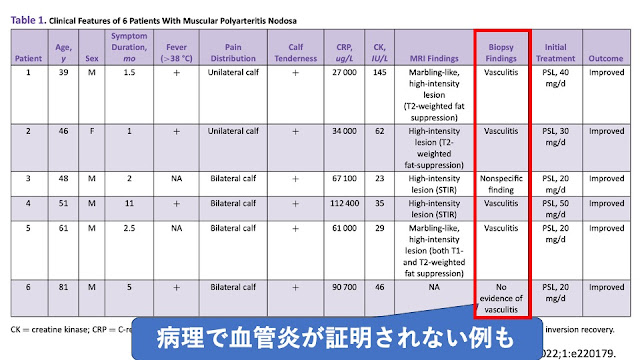

筋生検では血管炎の所見を証明することはできませんでしたが、

採取した部位が浅すぎて、血管炎を起こしている血管を拾えなかった可能性はあります

結局、下肢限局型のPNとしてステロイドで軽快しています